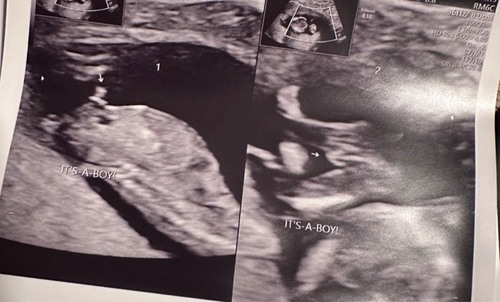

Hier ook tijdens de 13 weken echo heel duidelijk een jongetje! Ik ben nu bijna 38 weken. Volgens alle echo’s is het nog steeds een jongen 😜

Bij ons kon de verloskundige met 11 weken al zien dat het een jongetje was. Ze gaf aan dit vrijwel zeker te weten en dat het haar zou verbazen als het anders zou zijn. Ze bleek gelijk te hebben.

Bij ons met de 13weken echo volgens de echoscopist 100%zeker meisje, met de 20weken echo nog een x gekeken, echt een meisje!

Mijn partner vroeg het na afloop. Nadat we wisten dat alles okee was. Zelf heb ik niks gezien en ook niet op gelet. Ik ging er vanuit dat ze het niet wilde zeggen. Maar ze zei "wil je het echt weten? Want ik heb een vermoeden" en toen dus "ik denk dat het een jongetje is". En toen was ik eigenlijk best in shock haha.